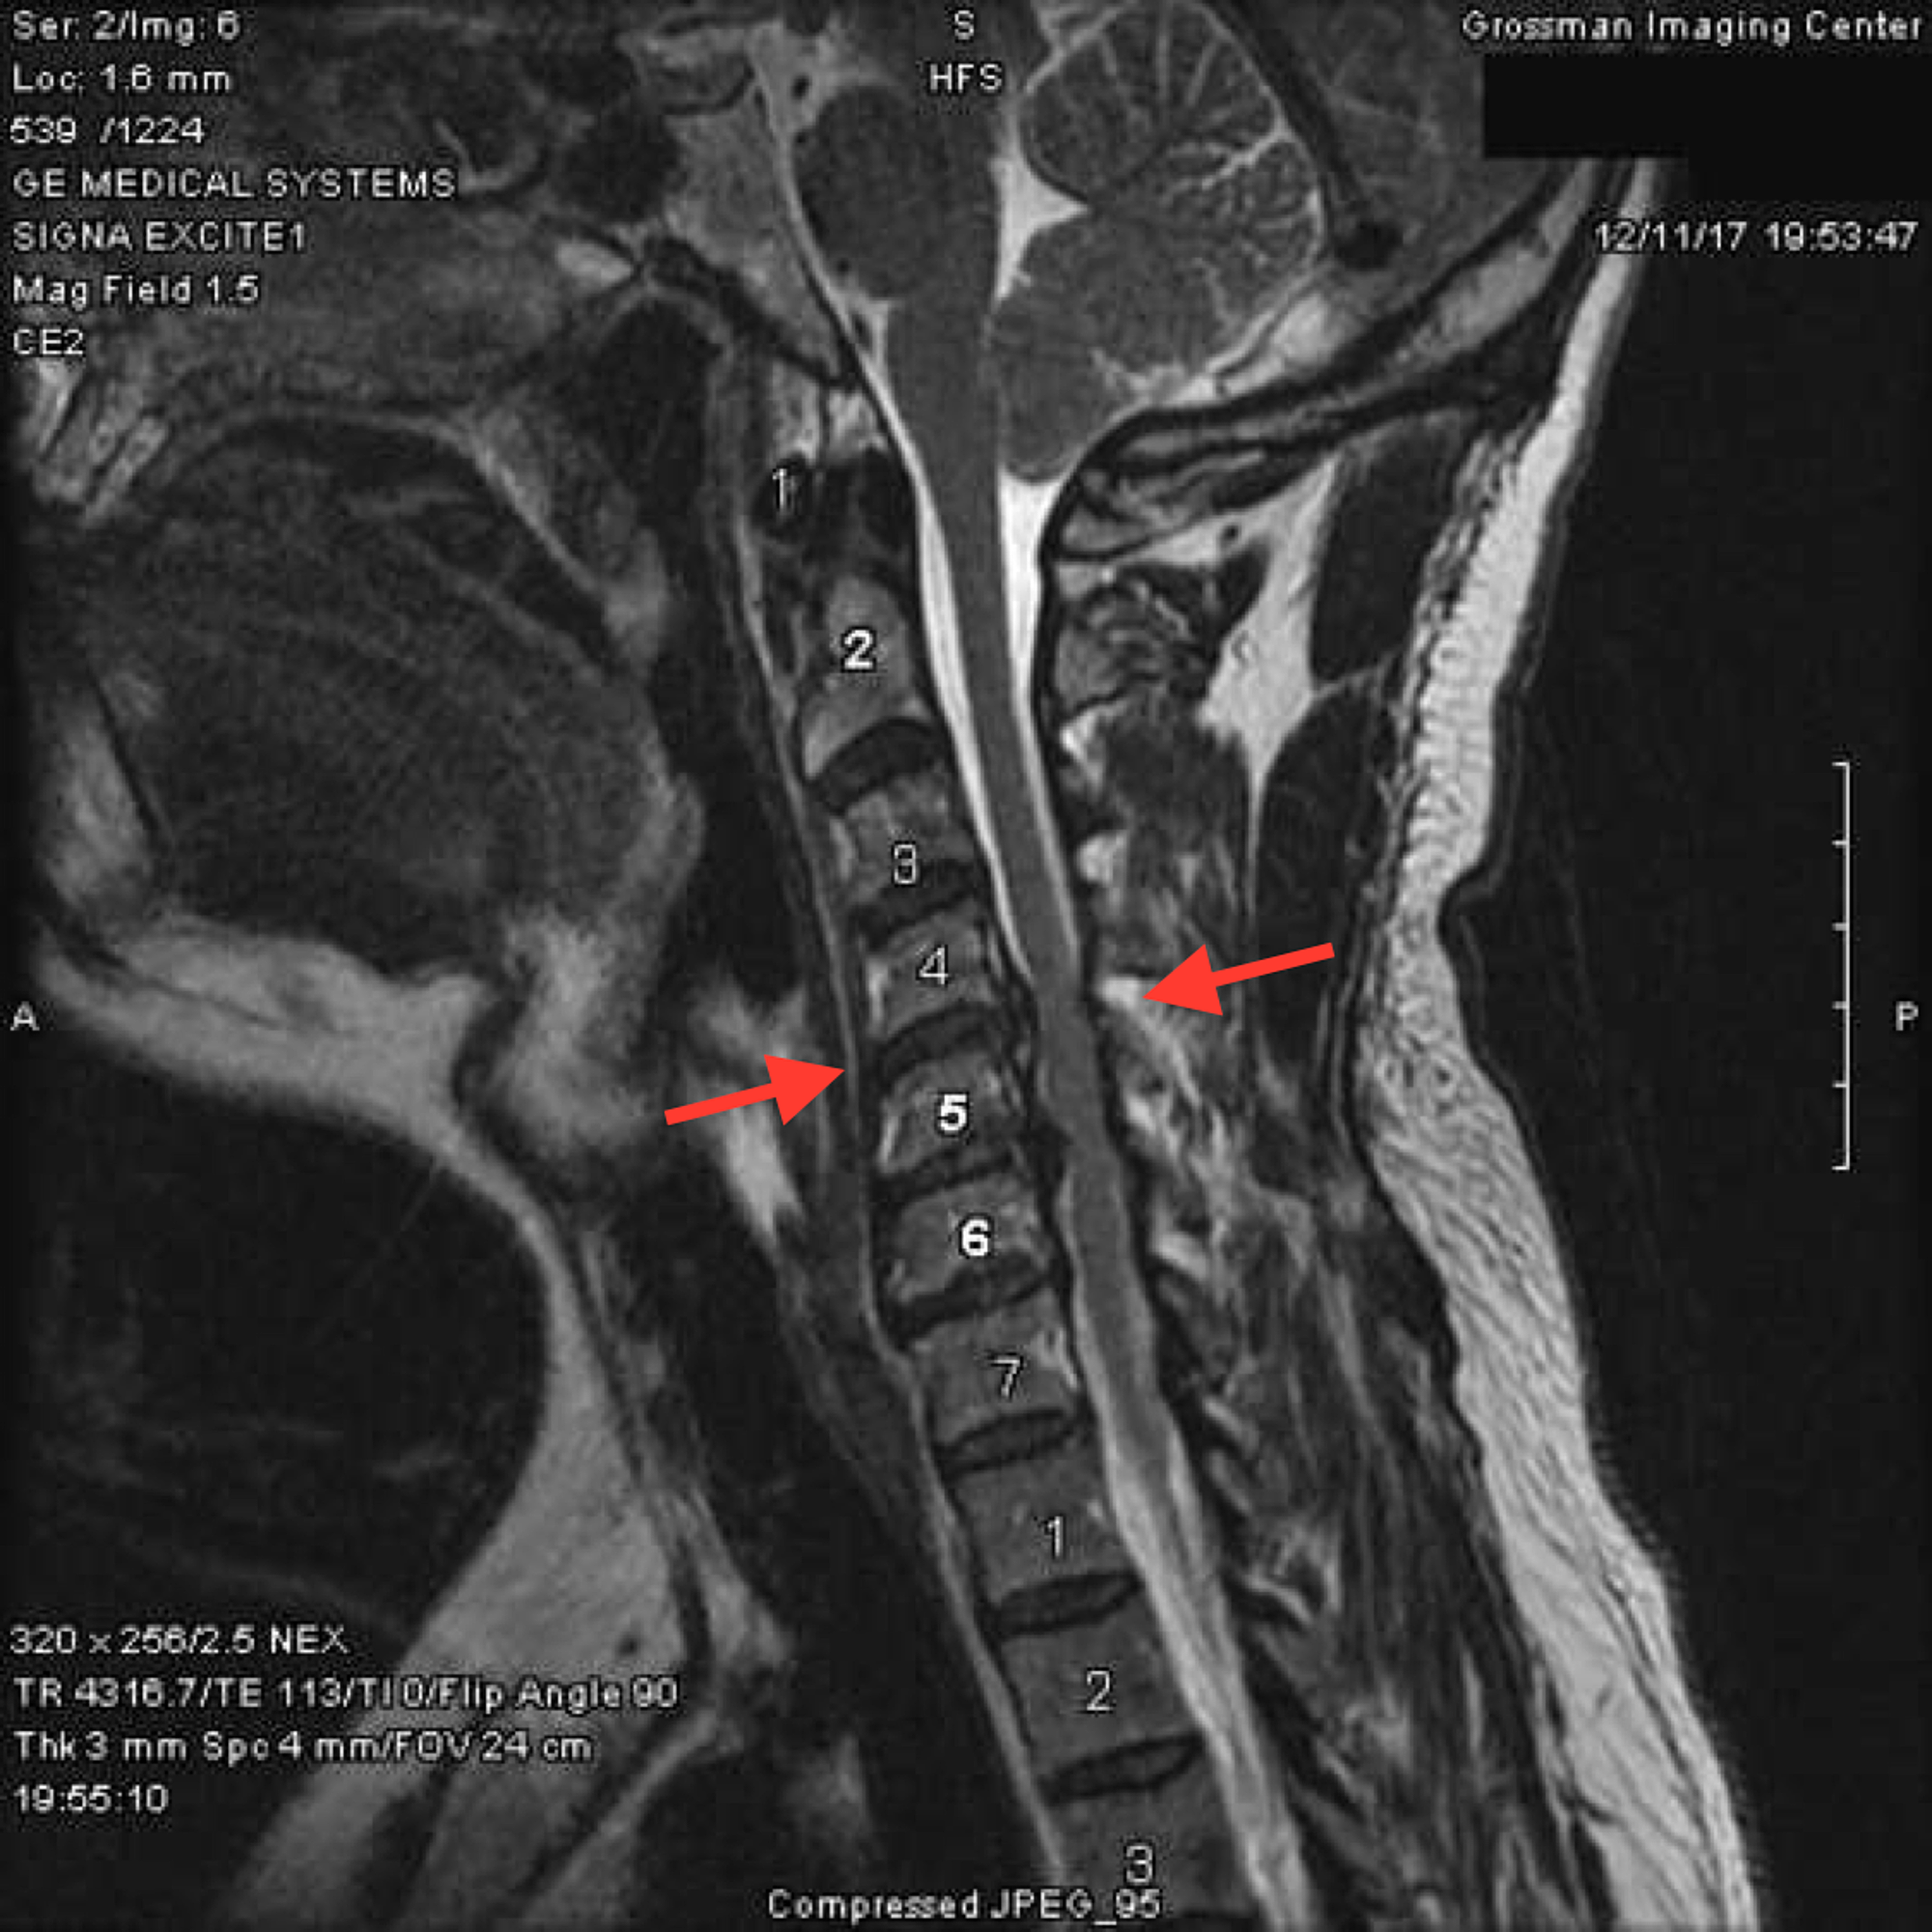

Cervical Spine Fusion Hardware Titanium Rods Spinal Fusion Mri Some physicians, however, have questioned whether titanium implants are actually safe for mri examinations. Magnetic field interactions, heating, and artifacts) are. Most people who have metal rods and screws inserted during spinal surgery can have a magnetic resonance imaging (mri) scan. Mri also allows assessment of scar tissue. Parallel rods connect fixed titanium posterior pedicle screws. Implanted devices can cause. Titanium Rods Spinal Fusion Mri.